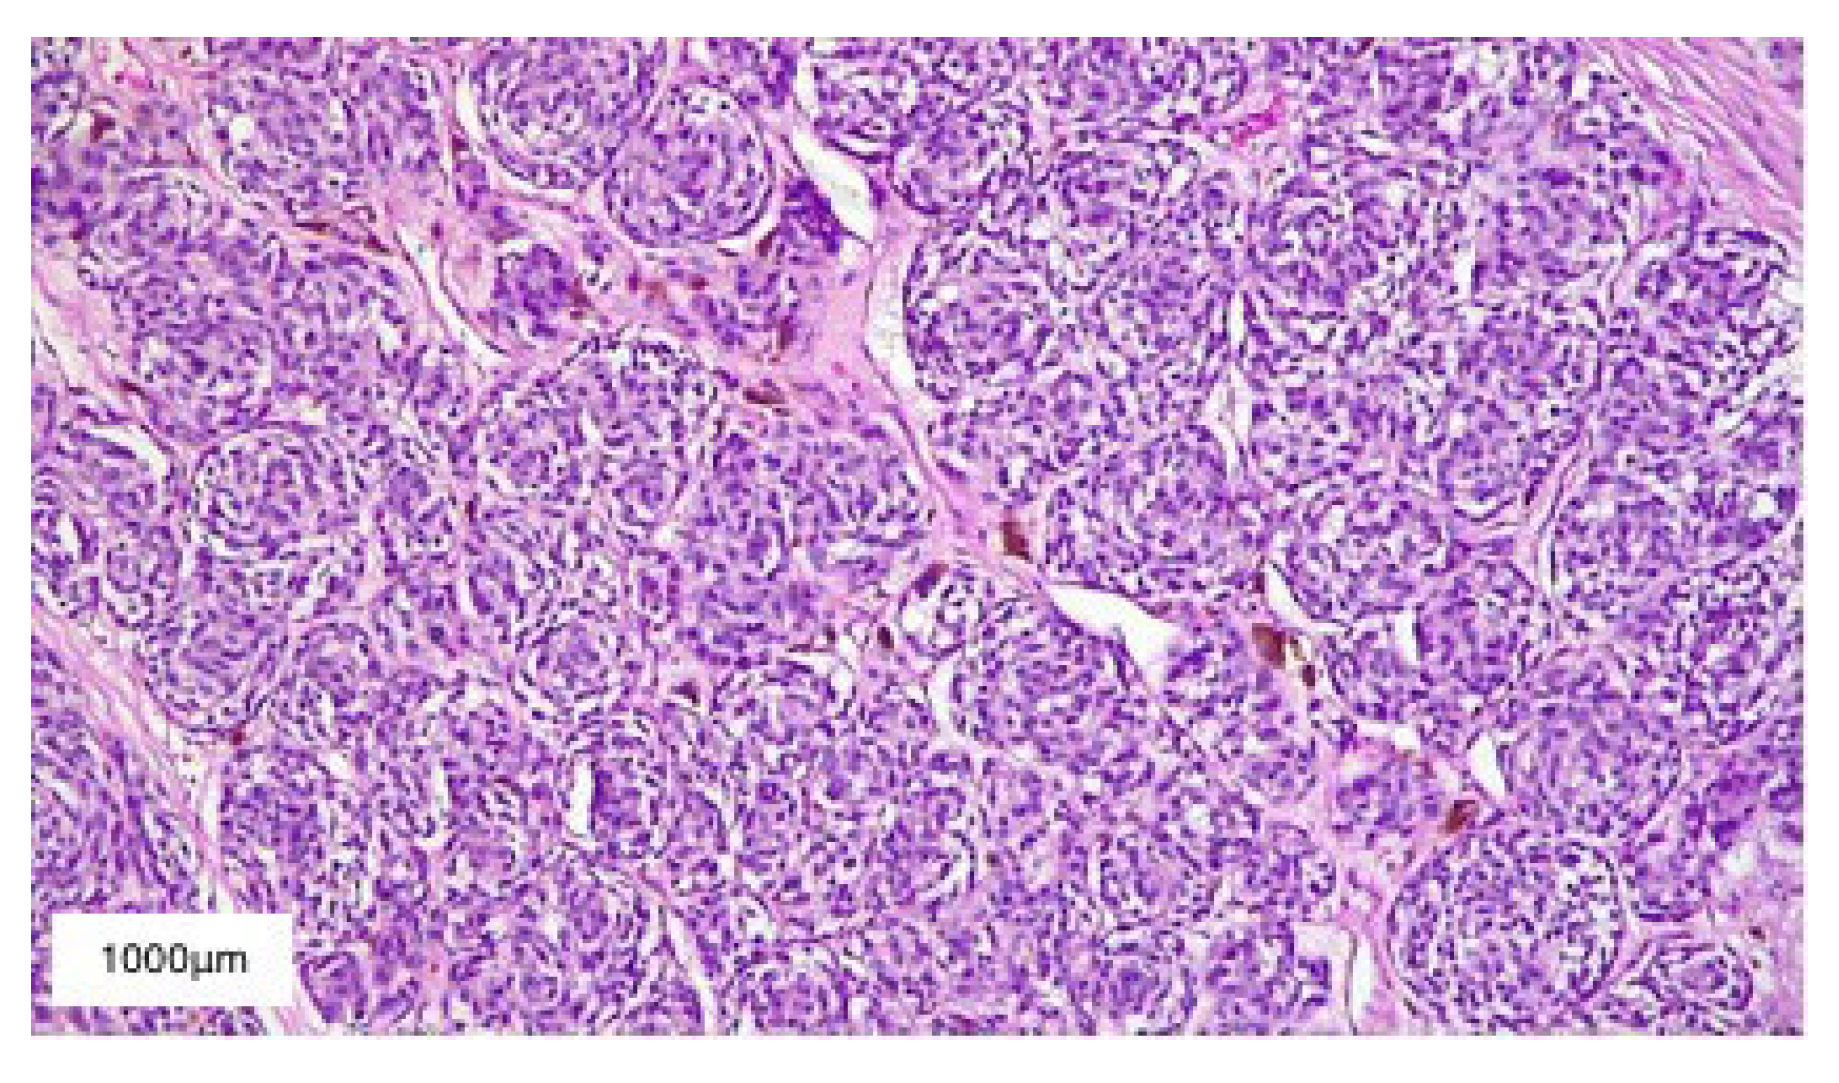

2. Case Presentation

3. Results